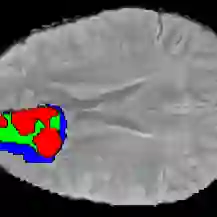

Current research on deep learning for medical image segmentation exposes their limitations in learning either global semantic information or local contextual information. To tackle these issues, a novel network named SegTransVAE is proposed in this paper. SegTransVAE is built upon encoder-decoder architecture, exploiting transformer with the variational autoencoder (VAE) branch to the network to reconstruct the input images jointly with segmentation. To the best of our knowledge, this is the first method combining the success of CNN, transformer, and VAE. Evaluation on various recently introduced datasets shows that SegTransVAE outperforms previous methods in Dice Score and $95\%$-Haudorff Distance while having comparable inference time to a simple CNN-based architecture network. The source code is available at: https://github.com/itruonghai/SegTransVAE.